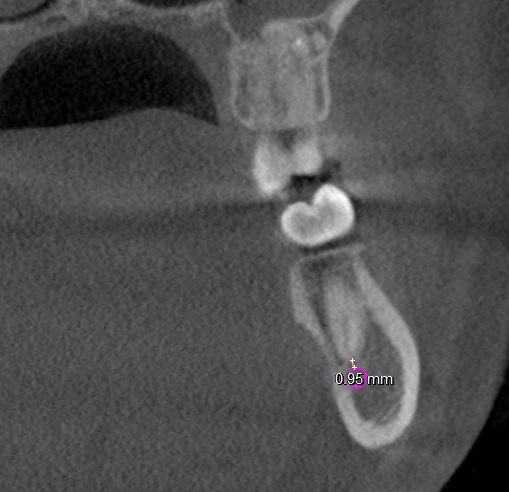

All molar teeth were evaluated in 3 planes (sagittal, axial and coronal) to determine the shortest linear distance between the root apex and the superior cortical border of MC (Figure 1). Distances <1.00 mm were classified as very close to MC (Figure 2).28 Distances ≥1.00 mm were considered distant from MC (Figure 3).28 When the root apex was in intimate contact with or invading MC, the distance was recorded as 0 mm (Figure 4).